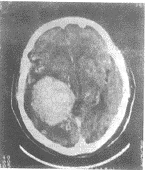

图4 脑膜瘤

CT增强横断位示右侧脑室三角区内巨大圆形肿块明显强化,呈均匀高信号